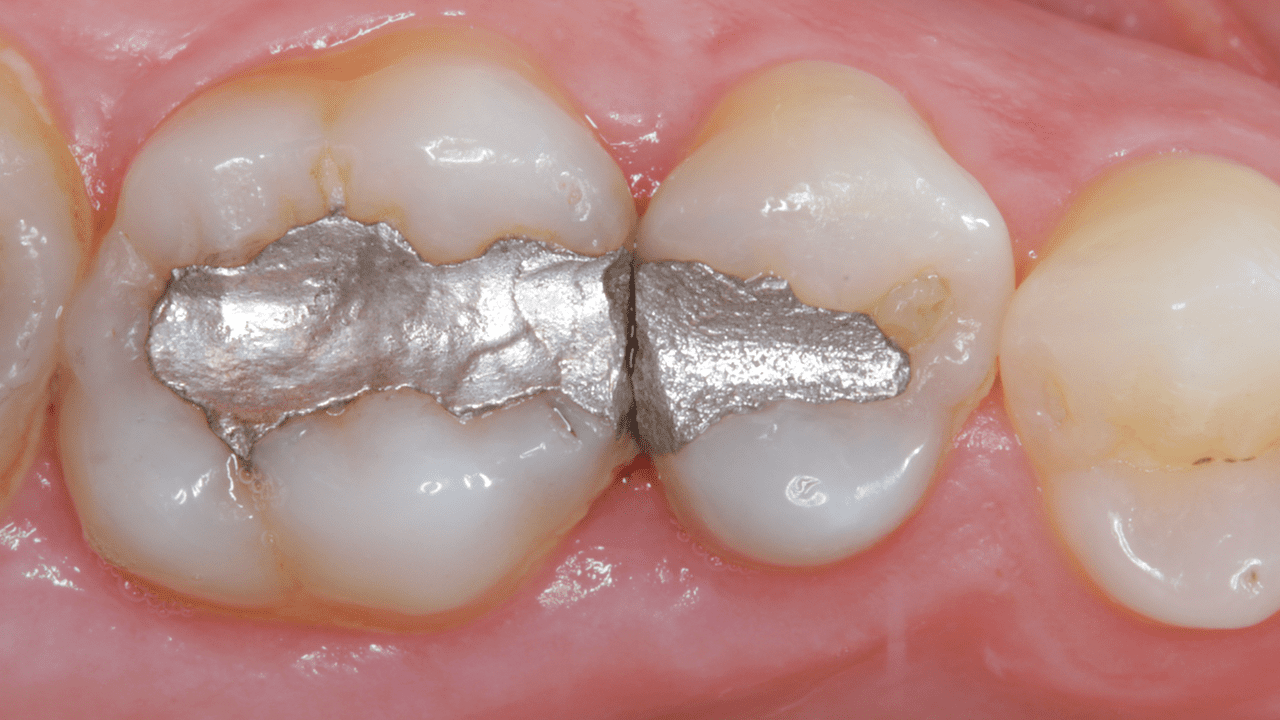

Случай: При первом осмотре были обнаружены неудачные старые реставрации амальгамой, утратившие герметичность.

Результаты: Повторный осмотр через 2 недели. Была выполнена окончательная реставрация с применением универсального композита Neo Spectra ST (оттенки A2 и BW), что позволило сохранить блеск и вернуть зубу утраченную анатомию и эстетичный внешний вид.